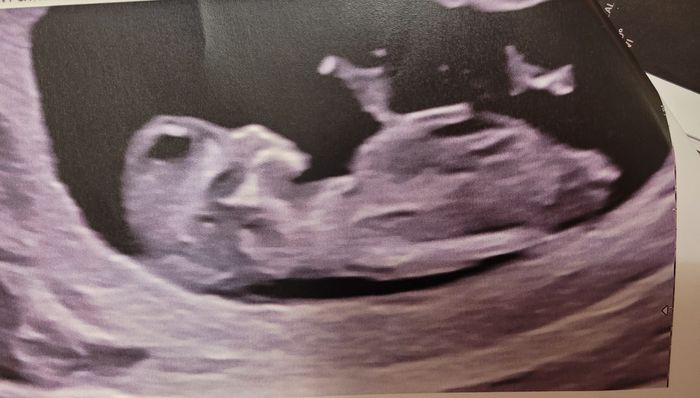

Ciao ragazze, lunedì scorso ho fatto eco genetica a 11+5 ma bebè misurava 12 settimane, ho fatto dna fetale che dovrebbe arrivare questa settimana, ma nel frattempo per ingannare il tempo e l’ansia, c’è qualcuna che se ne intende di nub theory? Io un pochino sì e quindi ho una mia idea. Sia per il tubercolo, sia per la posizione della vescica, rispetto alla spina dorsale… ma magari qualcuna qui ne capisce più di me, maschio o femmina?vi lascio un po’ di foto

Esatto, quello è precisamente il tubercolo. Vedi che ha quella punta che va in su? Ecco quella incrociata con la vescica mi fa dire maschietto: ma ripeto, potrebbero essere genitali gonfi a 11 settimane… anche se di lato non ci si sbagli facilmente: ma non potrei mai dire maschio con certezza perché la nub è attendibile dalle 11+5/12 in poi…. Prima è un po’ azzardato

Ti faccio vedere la mia nub così vedi la vescica dove sta e come si incrocia

La vescica di Ginevra era molto alta e il tubercolo piattissimo… formavano una linea praticamente parallela con la spina dorsale.

Ma qui lei misurava 12 settimane anche se ero 11+5, più attendibile..Vediamo che succede

Eh no non è lì il tubercolo, è quello dell’altra foto che si biforca… e la vescica è quell’ovale nero poco sotto. Bisogna incrociare la punta del tubercolo con la vescica, e tracciare la linea della spina dorsale… se l’angolo è maggiore di 35 per la nub è maschio..